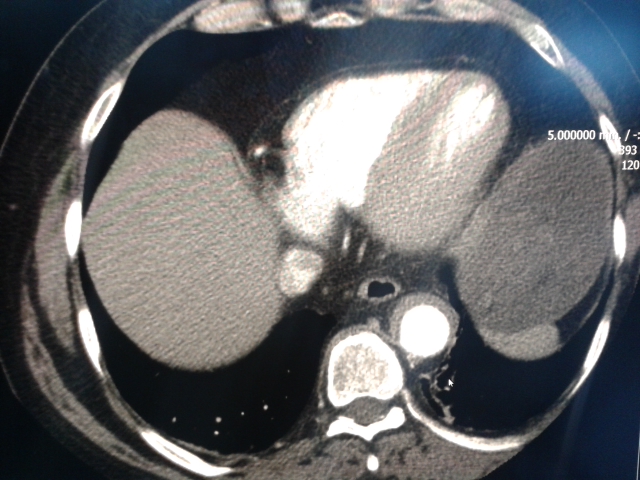

aorta4